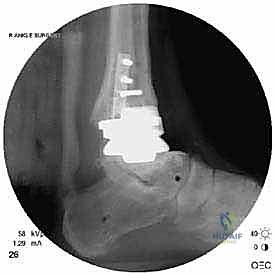

علاج هذه الكسور يتطلب مهارة فائقة من الدكتور محمد هطيف، حيث يتم استخدام تقنيات الجراحة الميكروسكوبية وتثبيت الكسور باستخدام صفائح معدنية دقيقة ومسامير (Locking Plates) دون المساس بثبات المفصل الصناعي، أو يتم دمج علاج الكسر ضمن عملية مراجعة المفصل الكلية إذا كان المفصل نفسه تالفاً.

تعتبر غرفة العمليات ساحة لإظهار البراعة الجراحية. عملية المراجعة تستغرق عادة من 3 إلى 5 ساعات وتتم عبر الخطوات المعقدة التالية:

يتم إدخال المفصل الجديد المخصص للمراجعة، والذي يحتوي غالباً على سيقان (Stems) تدخل عميقاً في عظمة الساق وعظمة الكاحل لضمان الثبات الميكانيكي. في حال وجود كسور في الكعب، يتم تثبيتها في هذه المرحلة.

الخطوة السادسة: الإغلاق التجميلي

يتم خياطة الأربطة والأنسجة الرخوة والجلد بطرق تجميلية دقيقة لتقليل الندبات وسرعة الالتئام، ثم توضع القدم في جبيرة خلفية واقية.